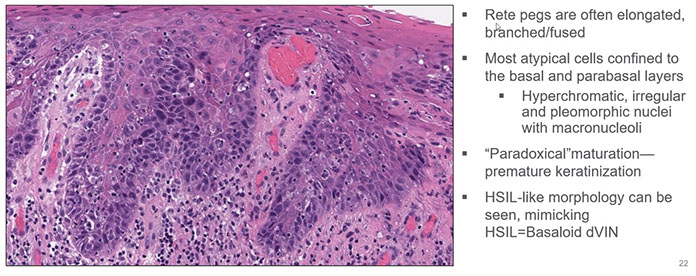

Type 2

Differentiated or Simplex subtype of VIN (dVIN) is a unique subtype seen in post-menopausal women presenting as an ill-defined gray-white plaque associated with lichen sclerosus, and more likely than warty to progress to invasive SCC and is high-grade by definition (regardless of extent of maturation)

- may not be recognized if bx too superficial, not assoc c HPV, assoc c cigarette smoking;

- usually a difficult dx to make bc often has overlapping features with b9 hyperplasia, lichen sclerosus and lichen planus

- frequently have p53 mutations

Micro: epidermis of dVIN usually thick and hyperkeratotic and/or parakeratotic with elongated and anastamosing rete ridges

- the basal cells show atypical, hyperchromatic nuclei often with inc mits

- upper layers made of enlarged squamous cells with abundant eosinophilic cytoplasm

Differentiated VIN

Differentiated VIN (dVIN) histopathology (Dr. Kang LASOP 6.14.22)

Basaloid dVIN mimicking HSIL (LASOP lecture 6/14/22)